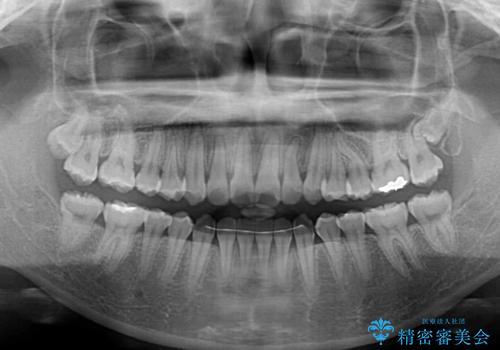

舌側転位している側切歯特有の、切縁の位置が不揃いであったり、根元が内側に引っ込んだ状態であったりという、インビザライン独特の仕上がりになることなく、きれいに整った歯列とすることができました。